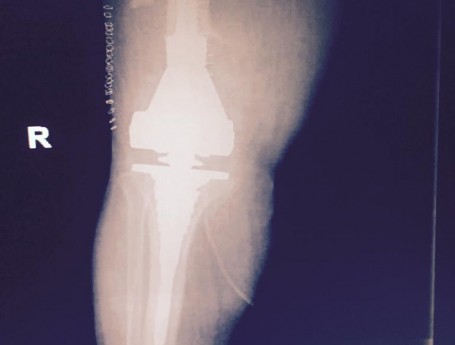

Total Knee Arthroplasty After a non-union